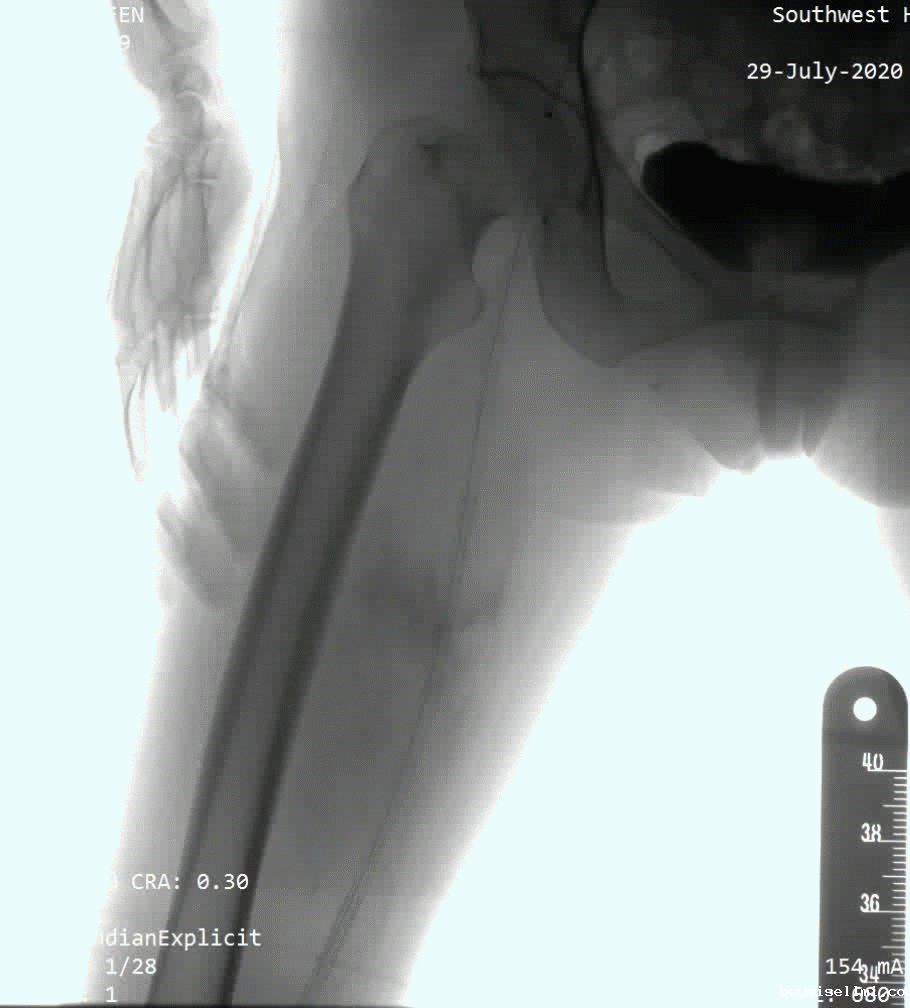

病例1:为股浅长段闭塞病变,术者采用了knuckle技术,选择Command 18导丝顺利通过病变。

病例2:为股浅长段CTO病变,术中多次尝试,开通极其困难,使用Connect Flex导丝后顺利通过闭塞段。

病例3:为Command 18联合Connect flex导丝顺利治疗的髂开口闭塞合并股浅长段CTO病变;术中首先采用逆向技术,穿刺股总动脉,开通髂动脉;随后使用Connect flex导丝顺利开通股浅远端长段CTO病变。